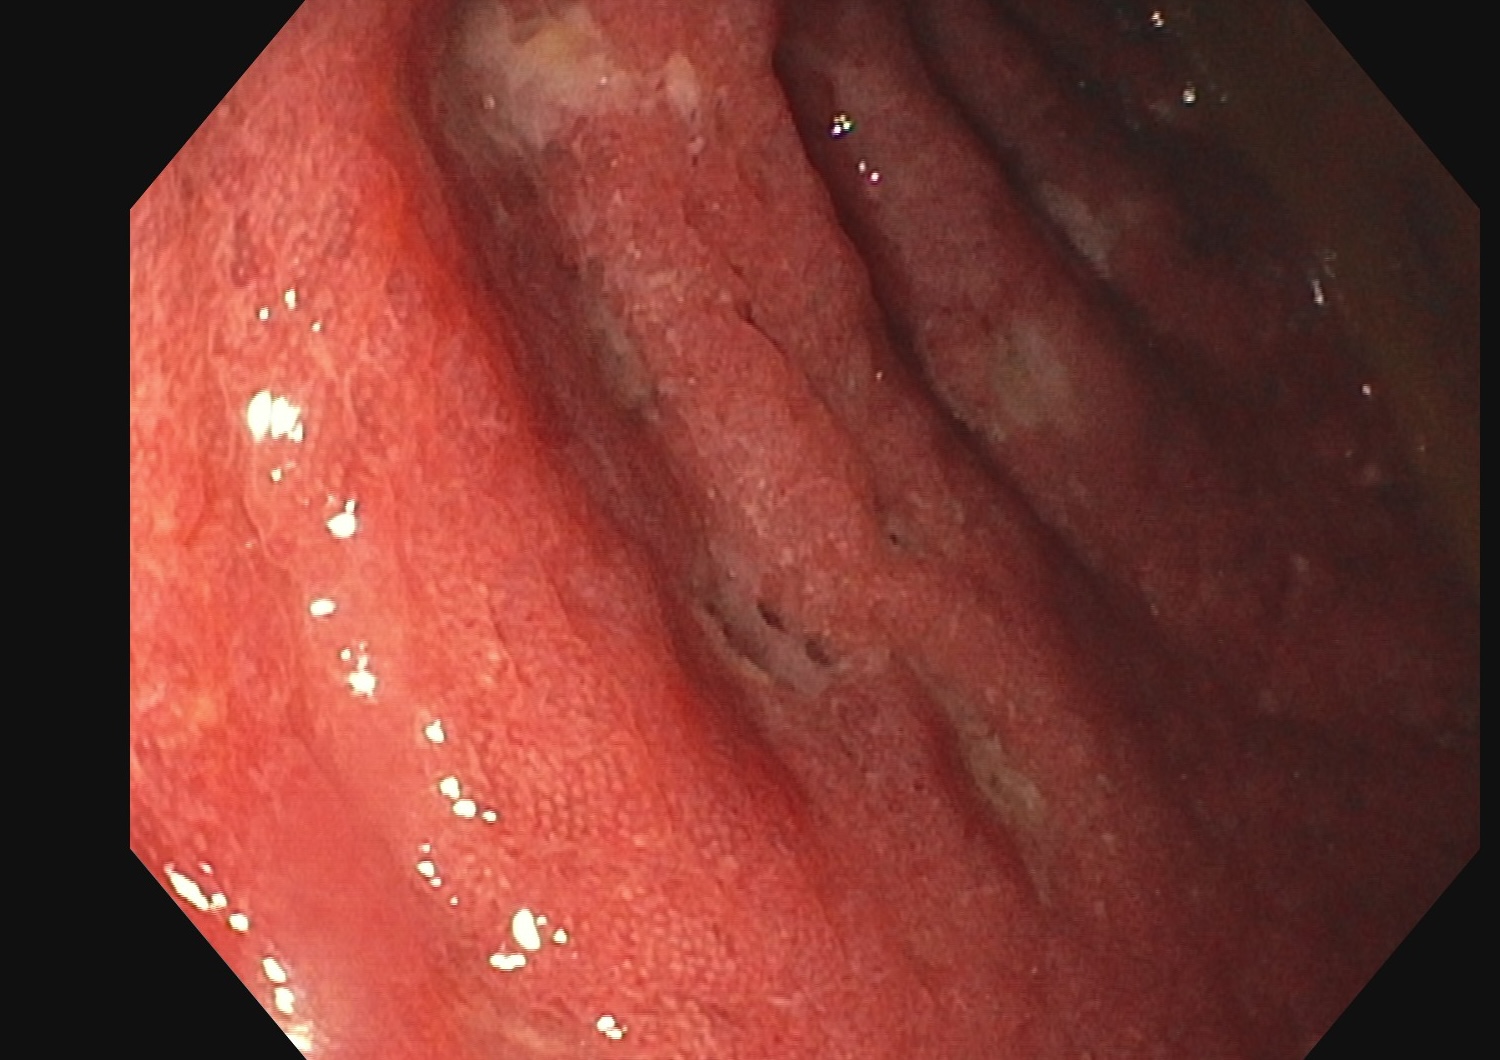

Endoscopie Mayo 3 UCESI 7/8 ulcères creusants

L’histologie confirme une RCH grave sans surinfection par le CMV.